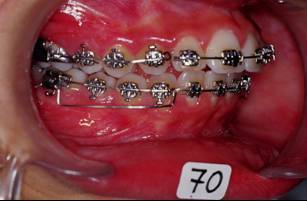

Pour finir j'etaits oblige de changer mon plan de traitement et accepter la solution par extraction de 4X4 et finir en classe I dentaire et legere tendance de classe II squelletique. L'ensemble du cas est tres acceptable, la patiente est tres contente, son sourir pas mal du tout, meme si ce n'est vraiment mon point de vu!!! Mais voila un cas ou j'etaits oblige d'extraire pour des raisons multiples, morphologie ethnique, maturation precoce, demande esthetique de la part de la patiente, des erreurs mecaniques de ma part? peut etre bien mais ca s'est passe comme ca... voici les photos

13 ipxuzs - Eugenol

14 f0gqim - Eugenol

15 myewxj - Eugenol

16 d66e2q - Eugenol

Suite et fin.

Il faut preciser une chose: Suivre un cas sur le forum ce n'est pas pareil comme vivre ce cas pendant le traitement. Le sourir fige sur photoo n'est pas aussi expressif et reel comme en clinic. La pression mise par les parents parfois est tellemnt forte qu'on finit par ceder.

Voila la fin de l'histoire...

17 hfdocf - Eugenol

18 aotm1c - Eugenol